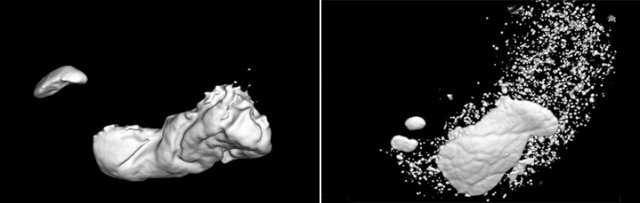

먹방이 신체에 어떤 결과를 가져오는지 동아일보 의학전문기자가 직접 체험해 봤다. 먹방 전후 위(胃) 모양을 3D CT(입체 컴퓨터단층촬영)로 찍어보니 결과는 충격적이다. 30배가량 늘어난 위 사진을 보는 것만으로 정신이 번쩍 들었다. 이번 먹방 도전에는 채널A 남혜정 기상캐스터도 함께 했다.

식사 전(왼쪽), 후 (오른쪽) CT 사진초밥 5인분을 먹은 뒤 신체 변화를 살폈다. 몸무게는 1시간여 만에 1.3㎏나 늘었다. 체질량지수는 24.2로 0.5가 증가했다. 놀라운 건 3D CT 사진이었다. 위의 부피가 350만6448㎣(약 3.53L)로 커졌다. 1시간동안 먹은 초밥 5인분에 위가 먹방 전보다 29.4배로 커진 것이다. 사람의 위는 보통 최대 4L까지 늘어나는 것으로 알려져 있다.

식사 전(왼쪽), 후 (오른쪽) 입체 CT 사진